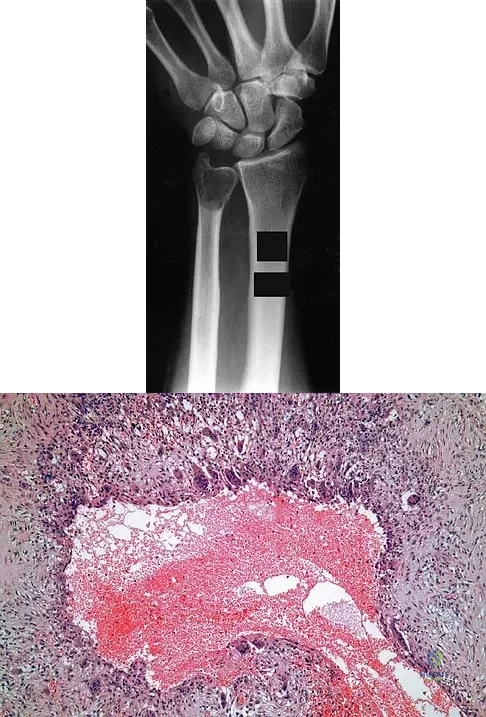

Question 12

A 30-year-old patient has wrist pain. A radiograph and biopsy specimen are shown in Figures 34a and 34b. What is the most likely diagnosis?

Explanation